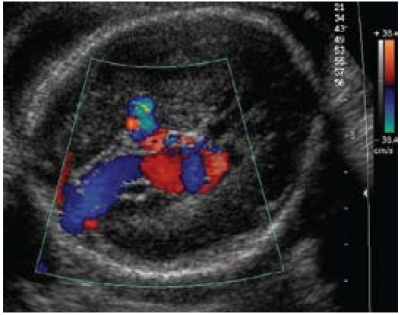

דופלר עוצמה (PD, Power Doppler) משפר את רגישות הזיהוי של קיום זרימה בהשוואה להדמיית דופלר צבע. שימוש בו בבדיקה בטנית או נרתיקית (Vaginal) מאפשר הדמיה מפורטת של המערכת העורקית והוורידית במוח העובר (תמונה 2). דופלר עוצמה יכול לשמש גם להערכת זילוח רקמתי אזורי במוח על ידי הערכת נפח הדם החלקי שבתנועה [14] (Fractional moving blood volume). בשיטה זו זוהו הבדלי אספקת דם לאזורים שונים במוח.